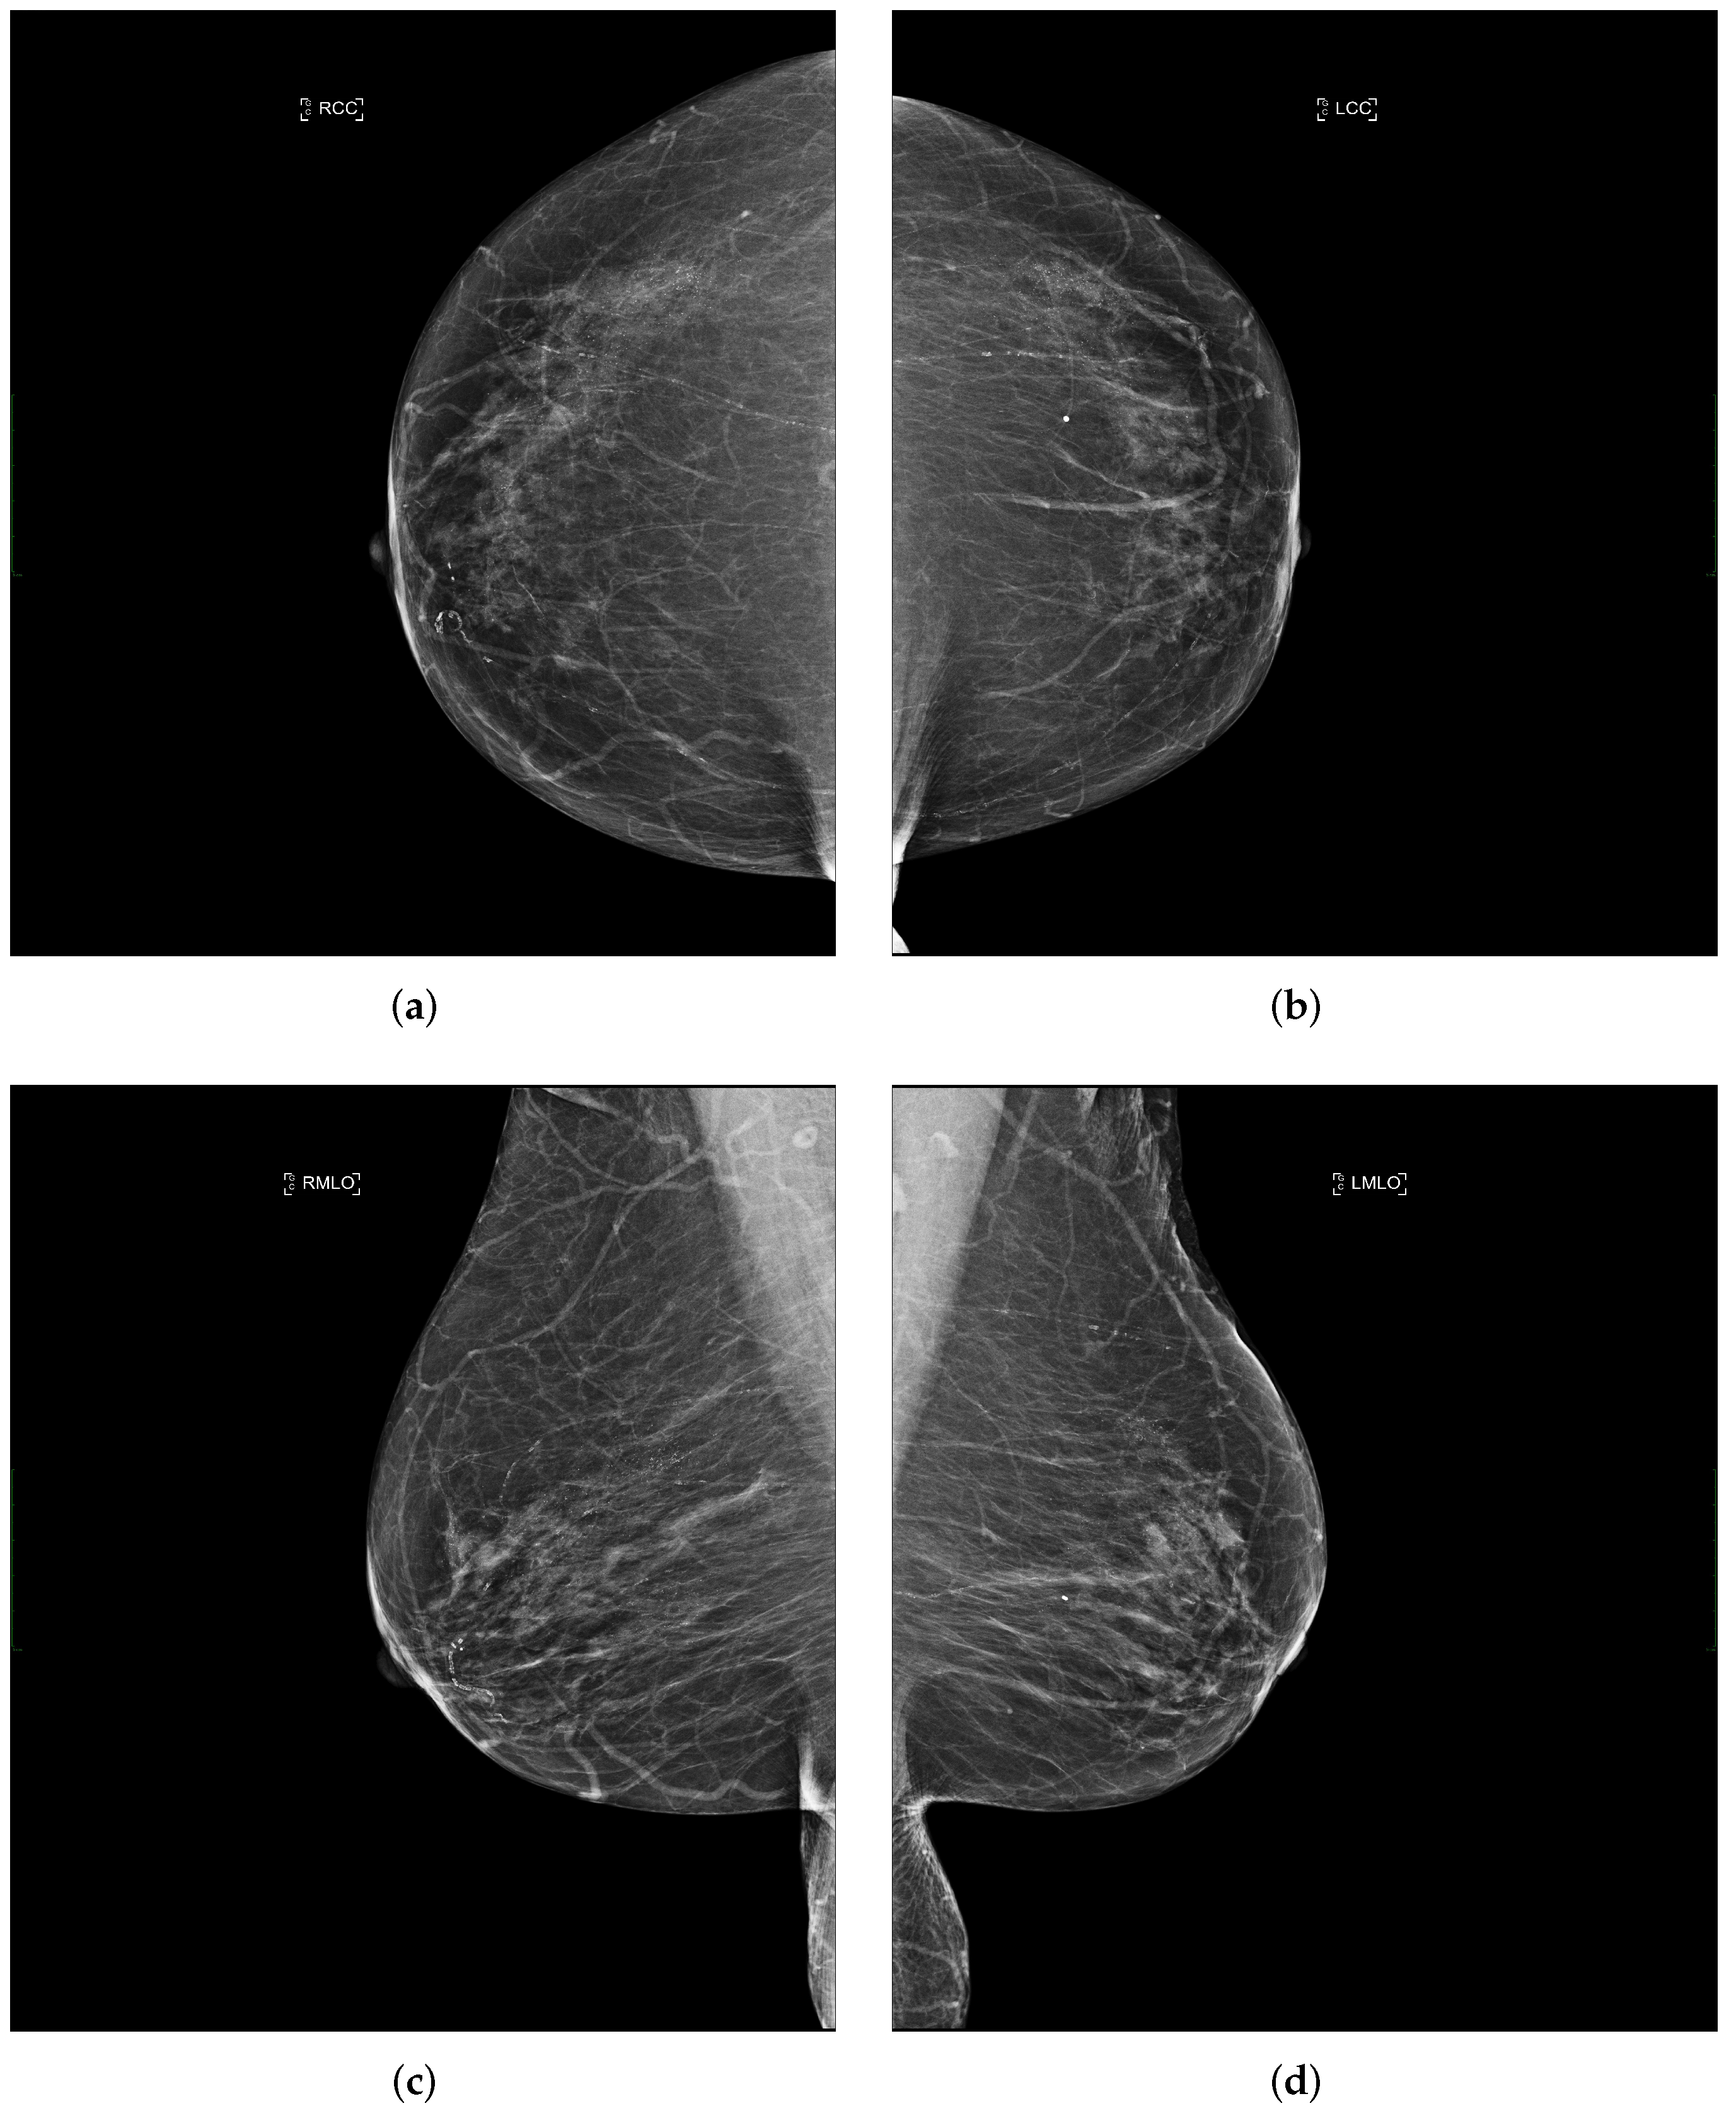

2.1. Mediolateral-Oblique View

2.2. Cranio-Caudal View